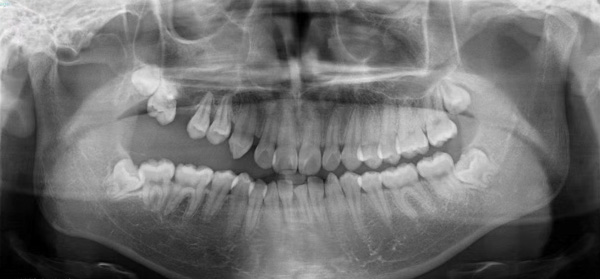

患者小潘(化名)是一名花季少年,5年前發(fā)現(xiàn)右側(cè)牙齒無(wú)法咬合,隨著年齡的增長(zhǎng),癥狀越來(lái)越嚴(yán)重,遂來(lái)到柳州市人民醫(yī)院口腔科就診,經(jīng)仔細(xì)檢查,確診為右側(cè)先天性頜骨畸形伴有上頜牙列缺損。

“上頜骨作為面中部1/3的骨性支撐,不僅決定了面中部的突度,還對(duì)患者的露齒、上牙中線的偏斜、牙合平面的偏斜等產(chǎn)生影響。”據(jù)口腔科副主任醫(yī)師劉彥杰介紹,該患者右側(cè)面部較左側(cè)面部較小,右口角向上歪斜,右上唇較左側(cè)薄,口內(nèi)咬合紊亂,右側(cè)開(kāi)牙合,右上頜高出頜平面3-5cm,右下頜舌傾。如果不加以干預(yù),可能會(huì)造成咬合紊亂加劇,面部愈發(fā)不對(duì)稱,甚至累及顳下頜關(guān)節(jié)導(dǎo)致顳下頜關(guān)節(jié)紊亂,最終影響面部頜口腔功能,進(jìn)食說(shuō)話都受到影響。